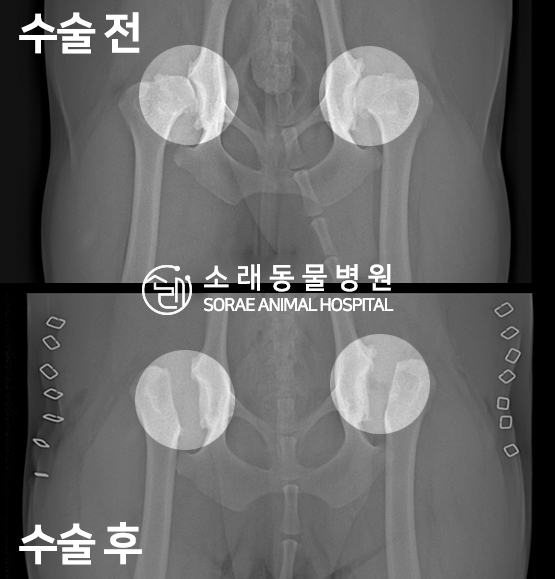

고관절 수술 사례 - #256 럭키

럭키는 고관절 이형성 수술 상담을 위해 내원하였습니다.

촉진 및 방사선 촬영 결과

대퇴골두 절골술(FHNO)이 필요하다고 판단되었습니다.

문제의 원인이 되는 대퇴골두를 깔끔하게 절단해 주었습니다.

수술 전과 수술 후 촬영한 고관절 방사선 사진입니다.

대퇴골두가 깔끔하게 절단된 것이 확인됩니다.

이제 재활 운동을 통해 체중을 지지할 근육을 키워주게 됩니다.